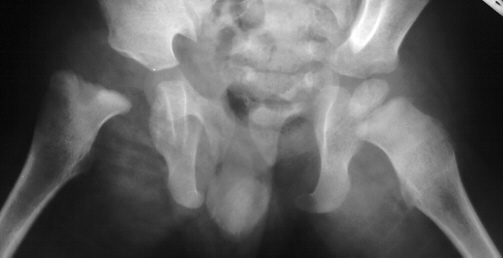

- Post Operative Day 18: R hip Xray: subluxation of R hip, possible metaphyseal

lucency consistent with osteomyelitis. Taken to OR for repeat I & D

Institute. Initial labs: WBC 15,100, ESR 72. R hip Xray: changes in proximal

. metaphysis including lucency and demineralization, hip subluxated. Treated

with oxacillin and Pavlik harness.